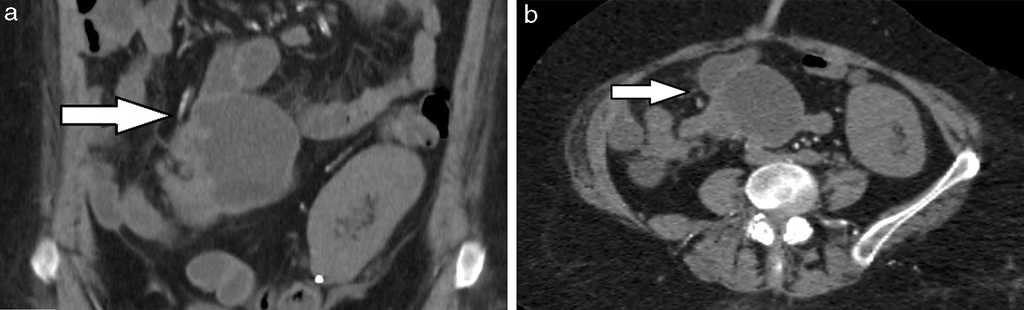

Sangrado (5%): se produce por erosión y ulceración de la mucosa en el interior del divertículo. Si bien la angiografía es el método de elección en casos de sangrado activo a fin de establecer su diagnóstico y eventual tratamiento sincrónico por vía endovascular, la TCMD muestra en la fase sin contraste restos hemáticos en su interior o signos de sangrado activo en la fase arterial1 (fig. 7).